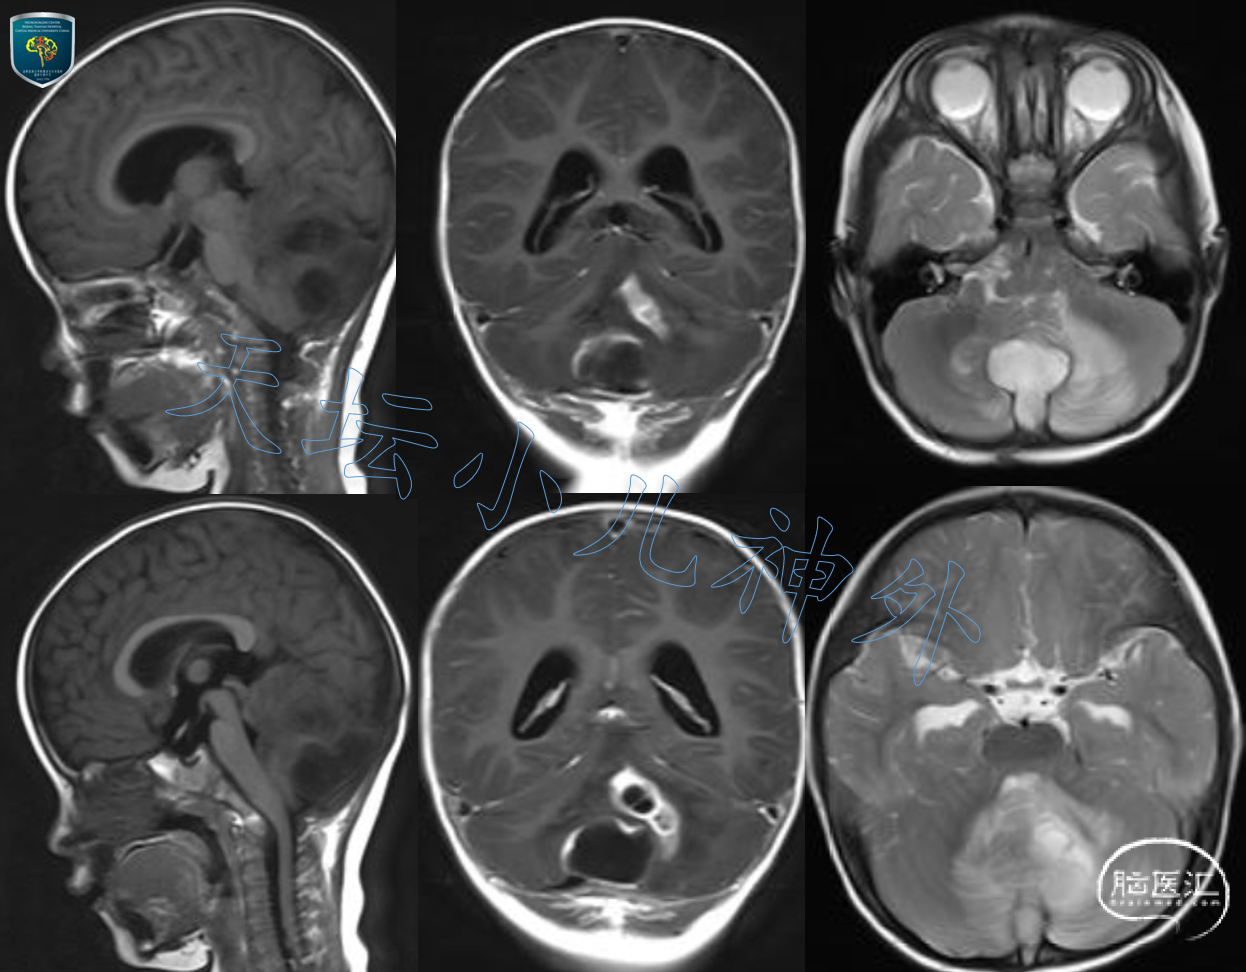

2020年10月接诊一例来自河北省保定市的1岁女性患儿(85cm,11.0kg)。主诉:枕后头皮感染清创术后3月,发现颅内占位一月余。患儿出生时发现枕部头皮小包块、表面生长有硬韧的毛发,未予重视。3月前局部外伤后枕部包块迅速增大,于当地医院行包块切除,术后高热,行头孢噻肟抗菌治疗20余天后好转,复查头部CT发现颅内占位,考虑髓母细胞瘤,遂来我院就诊。门诊查体示:患儿神情,精神状态好,查体欠配合,枕后局部切口愈合好,无红肿及溢脓溢液,余神经系统查体阴性。我院头颅CT显示:后颅窝中线团块状低密度影,边界模糊,密度不均,周围可见大片水肿区,大小约46X45mm(图1);头颅MRI提示后颅窝中线处长T1长T2病变,局部囊性变,囊壁光滑,边界不清晰,DWI呈显著弥散受限,多发囊腔显著环形强化,病变周围水肿明显,脑脓肿可能性大(图2)。

图2. 后颅窝中线处长T1长T2病变,局部囊性变,囊壁光滑,边界不清晰,DWI呈显著弥散受限,多发囊腔显著环形强化,病变周围水肿明显,脑脓肿可能性大。